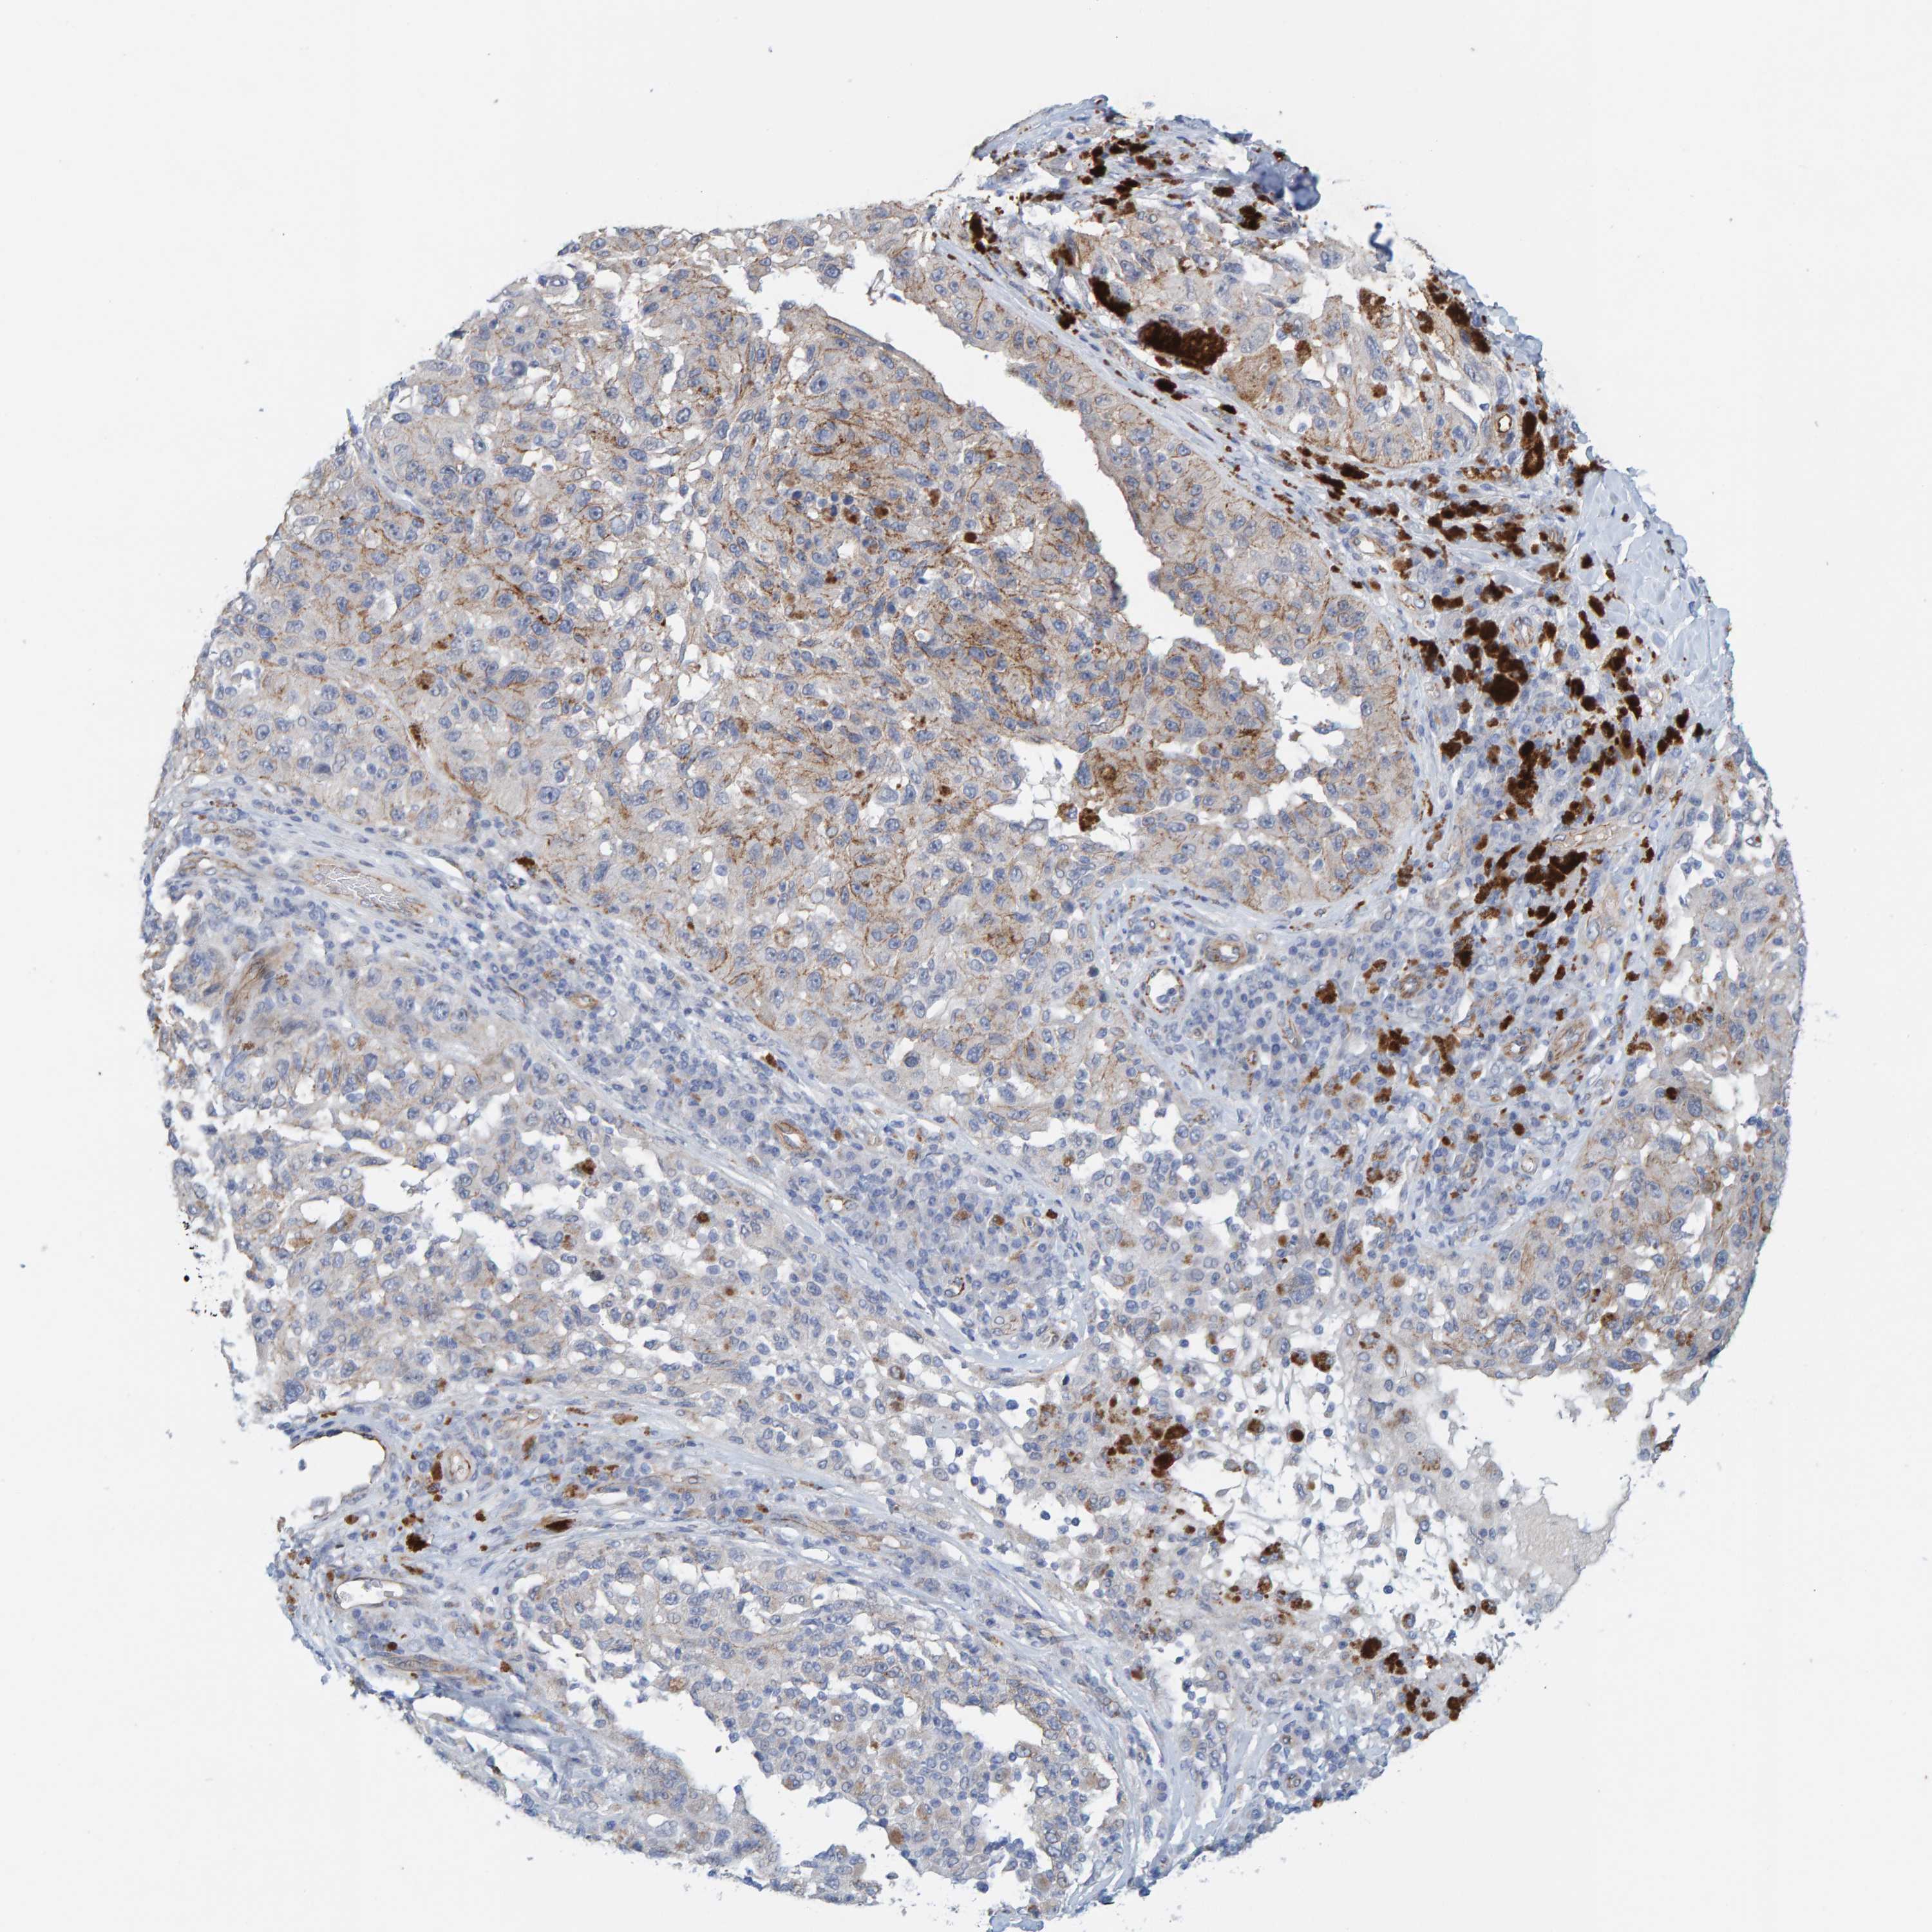

MELANOMA - Protein expressioni

A mouse-over function shows sample information and annotation data. Click on an image to view it in a full screen mode. Samples can be filtered based on level of antibody staining by selecting one or several of the following categories: high, medium, low and not detected. The assay and annotation is described here.

Note that samples used for immunohistochemistry by the Human Protein Atlas do not correspond to samples in the TCGA dataset.

Antibody stainingi

Antibody staining in the annotated cell types in the current human tissue is reported as not detected, low, medium, or high, based on conventional immunohistochemistry profiling in selected tissues. This score is based on the combination of the staining intensity and fraction of stained cells.

Each image is clickable and will lead to virtual microscopy that enables deeper exploration of all samples and also displays staining intensity scores, fraction scores and subcellular localization as well as patient and tissue information for each sample.

Antibody HPA022849

Staining

High

Medium

Low

Not detected

Intensity

Strong

Moderate

Weak

Negative

Quantity

>75%

75%-25%

<25%

None

Location

Nuclear

Cytoplasmic/membranous

Cytoplasmic/membranous,nuclear

Malignant melanoma, NOS

Malignant melanoma, Metastatic site